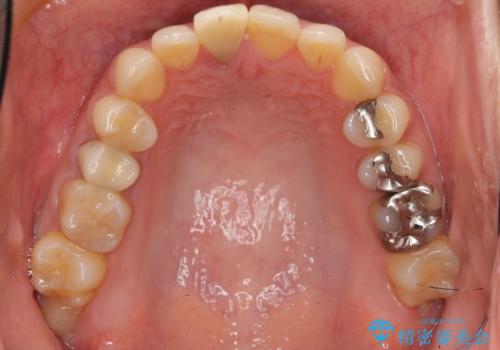

- もっと自然にみえるような差し歯にしたいと希望され来院された患者様です。

患者様の天然歯はグラデーションがあり切縁(歯冠の先端)はやや透けていて透明感があるのに対し、前歯(右上1)の差し歯はやや黄色く不透明で単調な色味でした。

患者様のご希望により、右上1はジルコニアクラウン(スペシャル)、右上5はジルコニアクラウン(スタンダード)へやりかえることにしました。